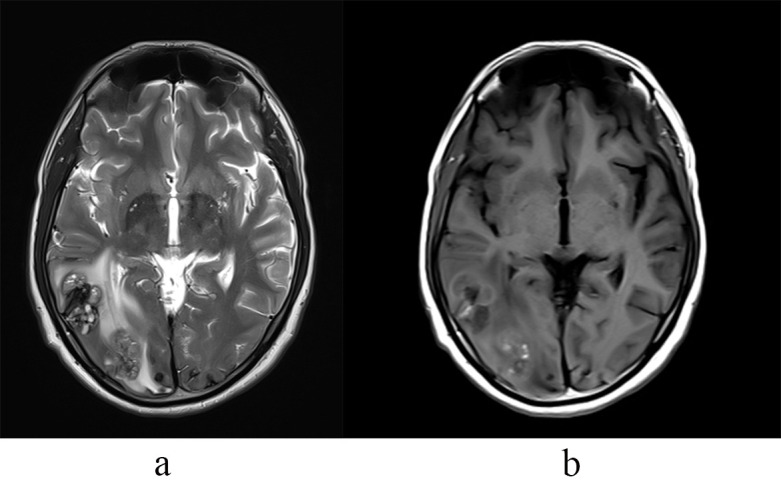

Unforeseen Sequelae: Myxomatous Aneurysm and Cerebral Metastasis in a Case of Atrial Myxoma-A Clinical Image.

不可预见的后遗症:1例心房黏液瘤的黏液瘤性动脉瘤及脑转移——临床影像。